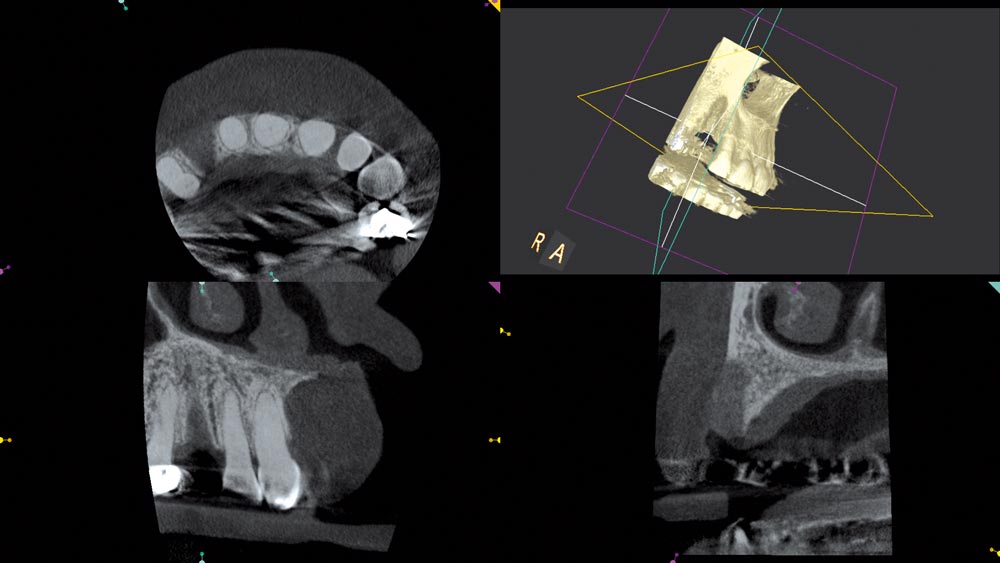

09/12 - CBCT scan 5 months post augmentation

Block augmentation with maxgraft® in the maxilla - PD Dr. Dr. F. Kloss